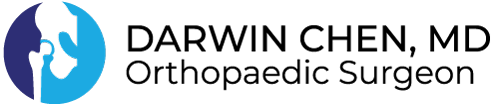

This is a 72 year old female with a history of diabetes and peripheral vascular disease who underwent total knee replacement 8 years ago. She did well with no issues. Unfortunately she developed systemic sepsis with Group B Streptococcus and presented with a month of knee pain. Her lab work, ESR and CRP, were elevated. Synovial fluid aspiration revealed WBC 7200, PMN 91%, and cultures positive for Strep agalactiae.

She underwent two stage exchange for infected TKA. During stage one, the prior knee implants were meticulously removed, and an articulated antibiotic spacer was placed using knee replacement implants, high dose antibiotic cement, and absorbable antibiotic beads. She was treated with IV antibiotics for 6 weeks. She underwent stage two reimplantation approximately three months later. The knee was reconstructed using a constrained condylar revision implant, hybrid/diaphyseal engaging stems, and a trabecular metal tibial cone.